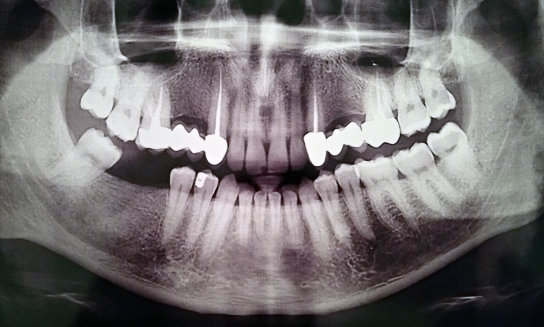

На каких зубах существует вероятность пульпита? 2. Есть ли вероятность, что на снимке присутствуют зубы, такие, что зуб значительно разрушен (от четырёх поверхностей), поэтому здесь требуется восстановление. То есть речь идёт о ситуации кариеса, когда пострадало более трёх поверхностей. Как известно, любой зуб имеет пять поверхностей (1. С внешней стороны. 2. С внутренней стороны (со стороны языка). 3. Со стороны левого соседнего зуба. 4. Со стороны правого соседнего зуба. 5. С жевательной стороны. Я понимаю, что точно диагноз нельзя поставить только по снимку, потому что нужен и визуальный осмотр, но речь идёт просто о возможности (подозрительных зубах и наиболее сложных).

Прям четких пульпитных явлений на снимке я не увидел. Шестой зуб сверху (26), требует установки коронки из-за большого количества пломбы, что по показаниям требуется реставрация вкладкой и коронкой. Не знаю про какой зуб идёт речь, но при разрушении коронковой части зуба более, чем на 50%, необходимо устанавливать коронки. Для более подробной консультации, обратитесь к стоматологу на очный приём.